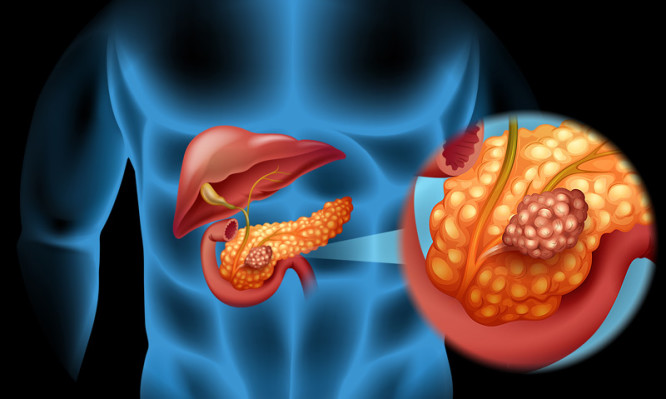

Ο καρκίνος του παγκρέατος είναι μια από τις πιο δύσκολα αντιμετωπίσιμες μορφές καρκίνου, με συνέπεια το προσδόκιμο επιβίωσης των ασθενών μετά τη διάγνωση να έχει αλλάξει ελάχιστα εδώ και δεκαετίες. Συχνά οι ασθενείς ζουν μόνο μερικούς μήνες, επειδή η νόσος είναι επιθετική, αντιστέκεται στη θεραπεία και διαγιγνώσκεται καθυστερημένα λόγω μη σαφών συμπτωμάτων.

Μόνο το 5% των ασθενών περίπου σήμερα ζουν για πέντε χρόνια, ενώ η νόσος εμφανίζει αυξητική τάση διαχρονικά. Περίπου 340.000 άνθρωποι διαγιγνώσκονται κάθε χρόνο με τη νόσο παγκοσμίως και άλλοι τόσοι περίπου πεθαίνουν, με τα υψηλότερα ποσοστά στις ΗΠΑ και την Ευρώπη.